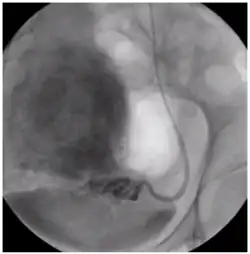

Восстановление кровотока в миоме через яичниковую артерию.

Эмболизация микрокатетером через яичниковую артерию.